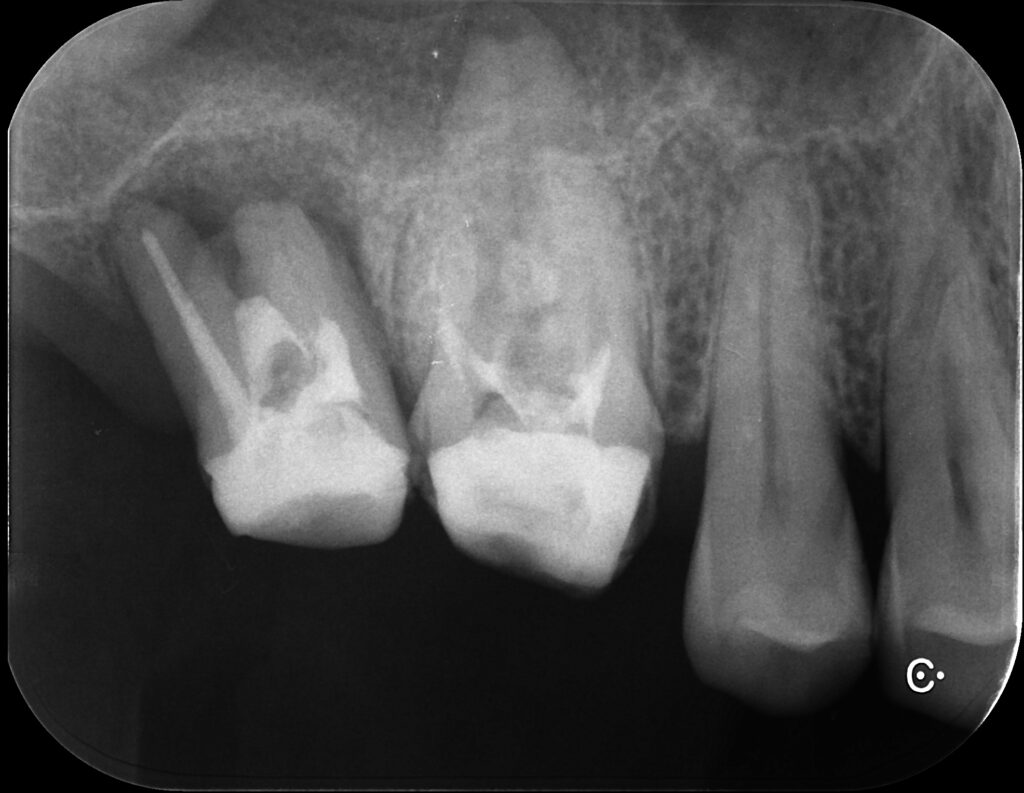

2年後

6年後

6年後はだいぶ根尖部にも骨ができてくれています。

7番の根分岐部(奥歯は根っこが複数あり、その股の部分)の

黒い部分は歯周病による骨の吸収なので仕方ありません。

ただし、痛みなどは全くなく噛めるそうです。

最初見た時はもう抜歯かなと思いましたが。